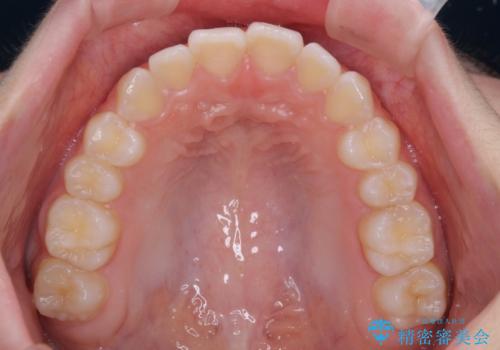

上下ともに少し捻れが残っていたため、治療の継続を提案しましたが、本人も親御さんも満足とのことで、治療を終えました。

捻れの改善により突出感も改善されました。